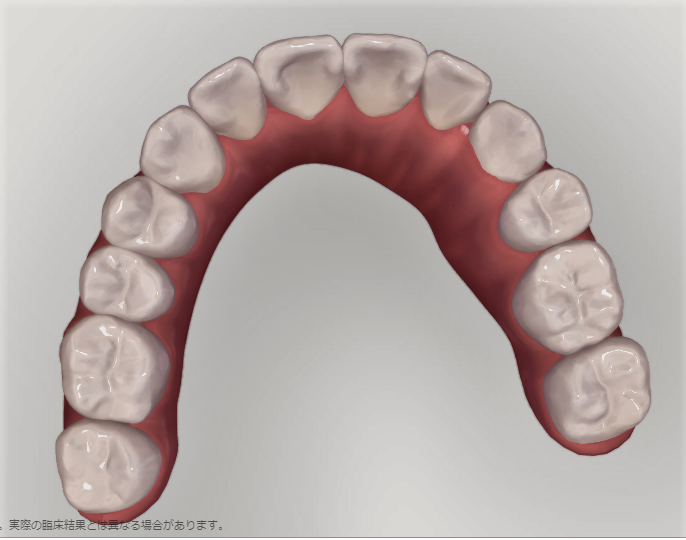

上の歯の比較